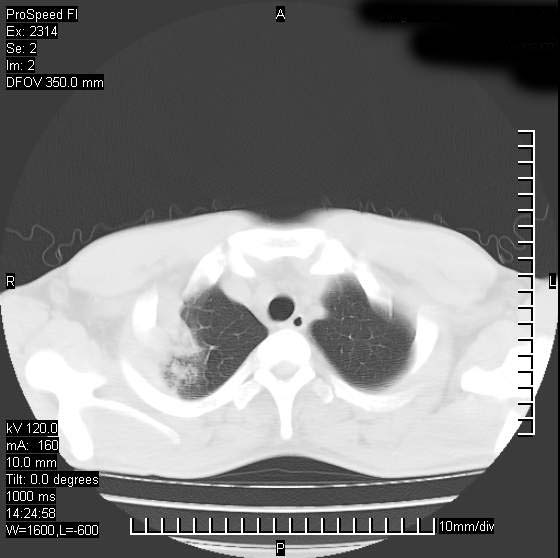

男性,再生障碍性贫血,入院前发热10天,最高40c,右侧胸痛,外院ct示右上,中肺边缘模糊的球性影(就是我现在图中标示的范围),考虑炎症,在我院使用头孢呋辛,洛美沙星10天,高烧消退,自感下午稍有发热,但今天ct示右上,中肺病灶明显扩大,还是考虑炎症,看其中的球型影是否霉菌感染??,是否能排除结核?

肺脓肿,伴双肺播散